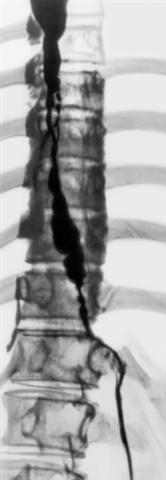

Рис. 10. Рентгенограмма пищевода при наличии послеожогового пищеводно-медиастинального свища: определяется затек рентгеноконтрастного вещества в средостение.